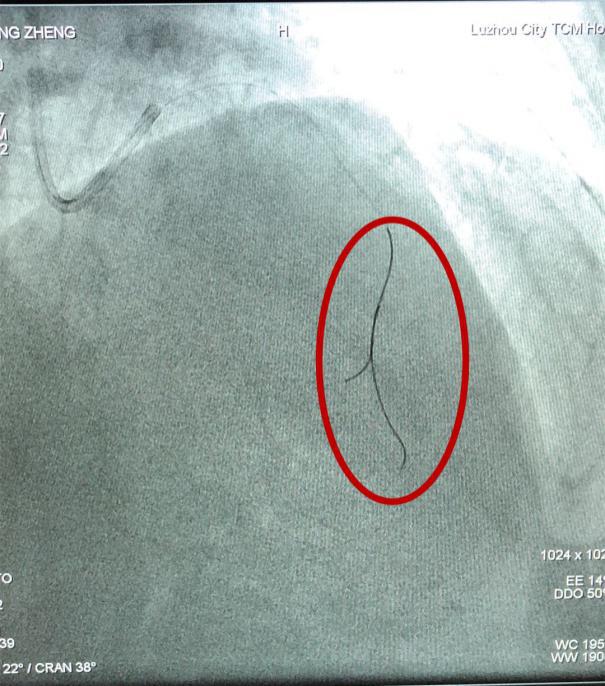

壓力導(dǎo)絲(如圖中紅圈內(nèi)所示)

在冠脈內(nèi)測(cè)量FFR(血流儲(chǔ)備分?jǐn)?shù))